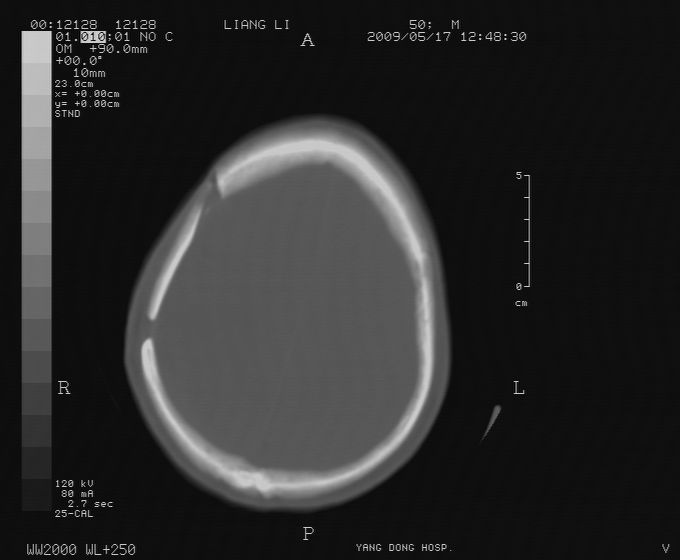

以下是引用zjzjr在2009-5-18 11:26:00的发言:[br]右颞枕叶及基底节区脑出血破入脑室系统,蛛网膜下腔出血,右枕顶部硬膜下血肿.颅骨及颅内低密度软化灶为血肿清除术后改变.

以下是引用随光逐影在2009-5-18 14:47:00的发言:[br]支持 右颞枕叶及基底节区脑出血破入脑室系统;蛛网膜下腔出血;右枕顶部及右侧天幕硬膜下血肿。右侧颅骨术后改变;颅内低密度软化灶为血肿清除术后改变。